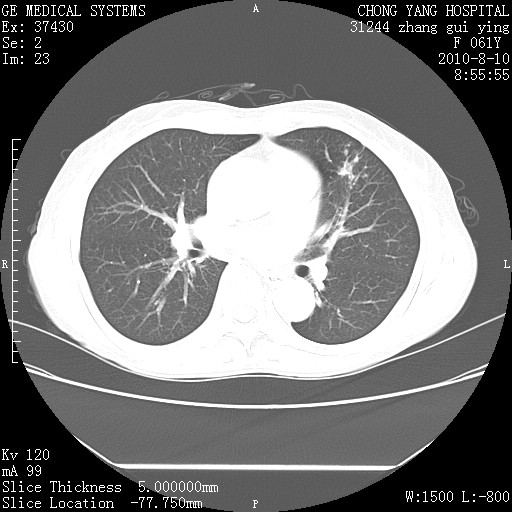

标题: CT28314:F61Y胸部增强,发热咳嗽一周入院,后面的为一周前平 [打印本页]

标题: CT28314:F61Y胸部增强,发热咳嗽一周入院,后面的为一周前平

1、支持考虑右侧中央型肺癌伴右肺中叶节段性不张及下叶支气管黏液痰栓    2、左肺上叶舌段感染。

支持右下肺中央型肺癌并左上肺感染.

支持3楼意见,还要考虑:纵隔及肺门淋巴结转移、右侧少量胸腔积液。

确切的说:1:右肺下叶中心型肺癌侵及中叶支气管并中叶不张,纵膈淋巴结转移。2:左肺舌叶炎症。3:右侧胸腔少量积液

块影平扫32hu,动静脉期62-70hu.